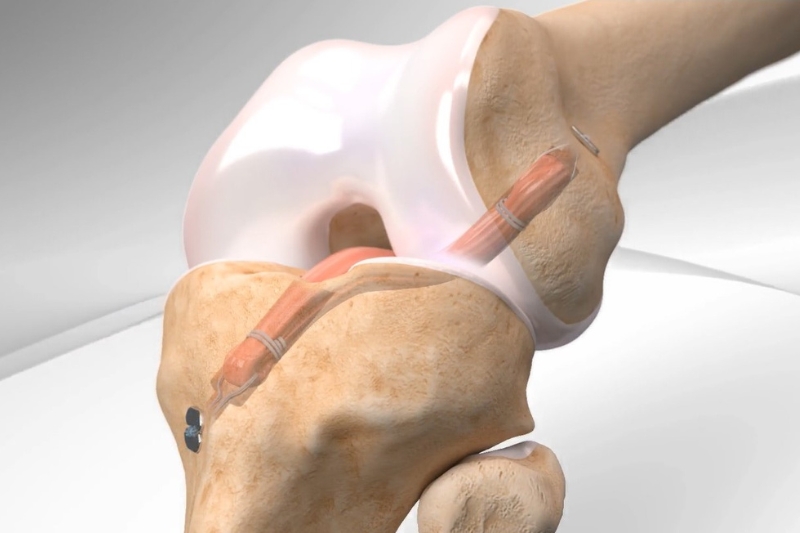

“All-inside” eljárás

Az All-inside egy minimálisan invazív eljárás, amelyet a térdízületi sérülések, különösen az elülső keresztszalag szakadás kezelésére alkalmazunk. Ez egy új módszer, Magyarországon Majzik doktor csinálja elsőként 2022 szeptembere óta.